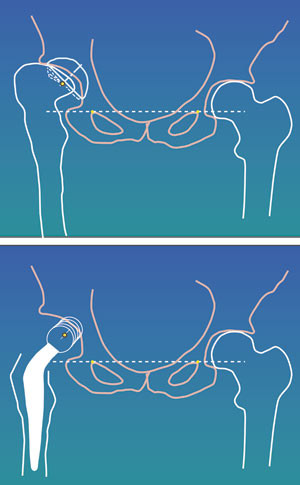

Pre- og postoperativ beinlengdeforskjell ble målt klinisk og røntgenologisk. Klinisk ble eventuell beinlengdeforskjell vurdert stående ved palpasjon av crista. For røntgenologisk vurdering trakk vi en linje mellom distale del av os pubis på hver side og vurderte senter av trochanter minor i forhold til denne linjen (5).

Harris’ hofteskår ble målt preoperativt og postoperativt etter ett år. Gjennomsnittlig skår preoperativt var 49 (spredning 27 – 66) og postoperativt 97 (spredning 76 – 100). Preoperativt var det aktuelle bein kortere (1 – 3 cm) hos 20 pasienter. Postoperativt var beina like lange hos 35 pasienter, hos én pasient var beinet fortsatt 1 cm for kort, og hos én pasient var beinet blitt 1 cm for langt (overkorreksjon). Eksempler på bruk av den individtilpassede hofteprotesen fremgår av figur 6, figur 7 og e-figur 8.